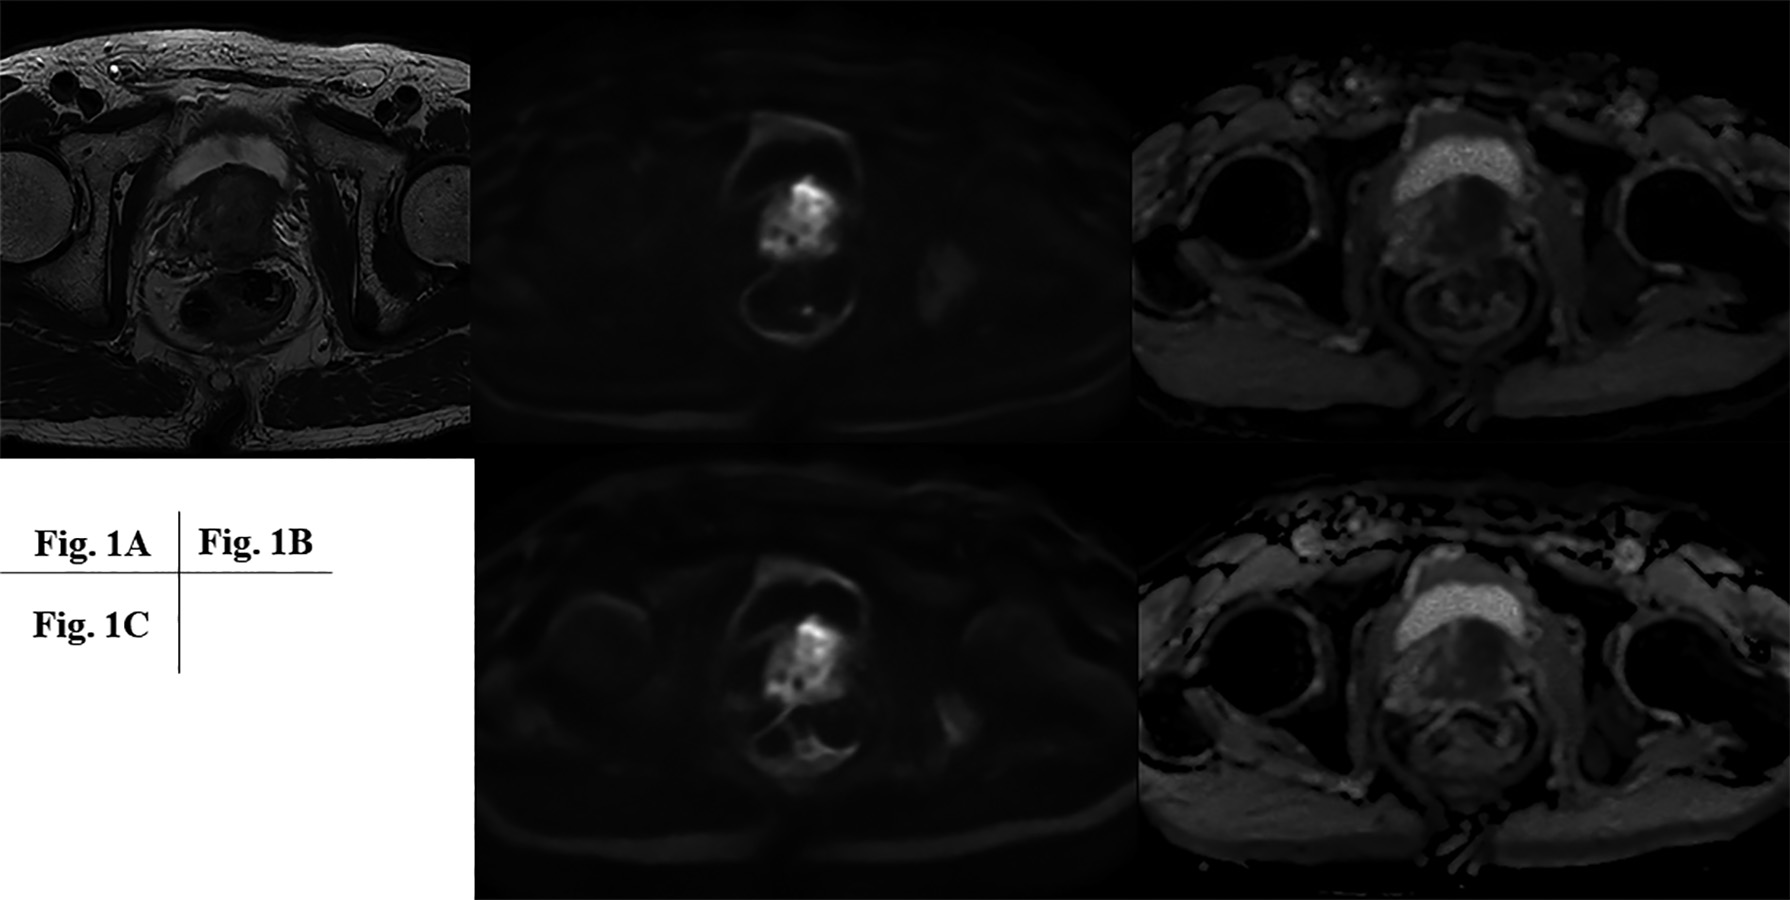

Figure 1. 78-year-old patient with prostatic cancer.

A: T2WI shows low signal intensity area from transitional zone to peripheral zone at basal level. B: (L to R: RDC DWI to ADC map from RDC DWI) Prostatic cancer is demonstrated as high signal intensity on RDC DWI and low ADC value on ADC map from transitional zone to peripheral zone at basal level. C: (L to R: RDC DWI to ADC map from DWI) Prostatic cancer is demonstrated as high signal intensity on DWI and low ADC value on ADC map from transitional zone to peripheral zone at basal level.